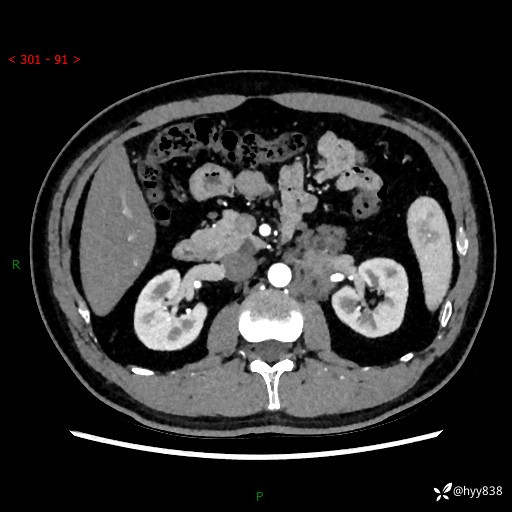

现病史:患者3月余前检查发现左侧腹膜后占位,大小约3.7*4.9cm,平素无腰疼,无肉眼血尿,无尿频尿急等不适,当时未特殊处理,在门诊复查CT提示左侧腹膜后占位,门诊拟“左侧腹膜后占位”收入院。 起病以来,患者精神佳,饮食、睡眠良好,大小便正常,体力体重无明显变化。

腹膜后CT平扫+增强